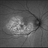

- macula serpiginous choroidopathy, Optos, fundus autofluorescence (FAF), macula lesion, ultra-wide field imaging, fundus photograph

- Optos ultra wide field auto fluorescent image of 20-year-old female presenting with serpiginous choroidal atrophy. Patient was unaware of vision loss OD, until accidentally covering OS and noticing the change. Acuity of 20/200 OD and 20/15 OS at time of imaging.